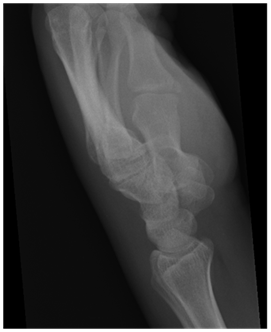

A severely angulated fracture of a metacarpal, avulsion of the metacarpal base or fracture of the hamate should also suggest the possibility of a carpometacarpal dislocation9 (Figure 4).

Figure 4 Lateral radiograph showing malalignment of the metacarpal bases suggestive of a dislocation.

Trauma lateral view radiographs of the hand can be difficult to interpret because of interposition of the carpal bones14,16 Compounding to this is the fact that the radiographer may not be able to position the patient for a true lateral view in a trauma setting due to pain or associated injuries.

On a true lateral radiograph with dislocation of carpometacarpal joints, the longitudinal axis of the involved metacarpal(s) does not parallel the axis of uninvolved metacarpals.2,17